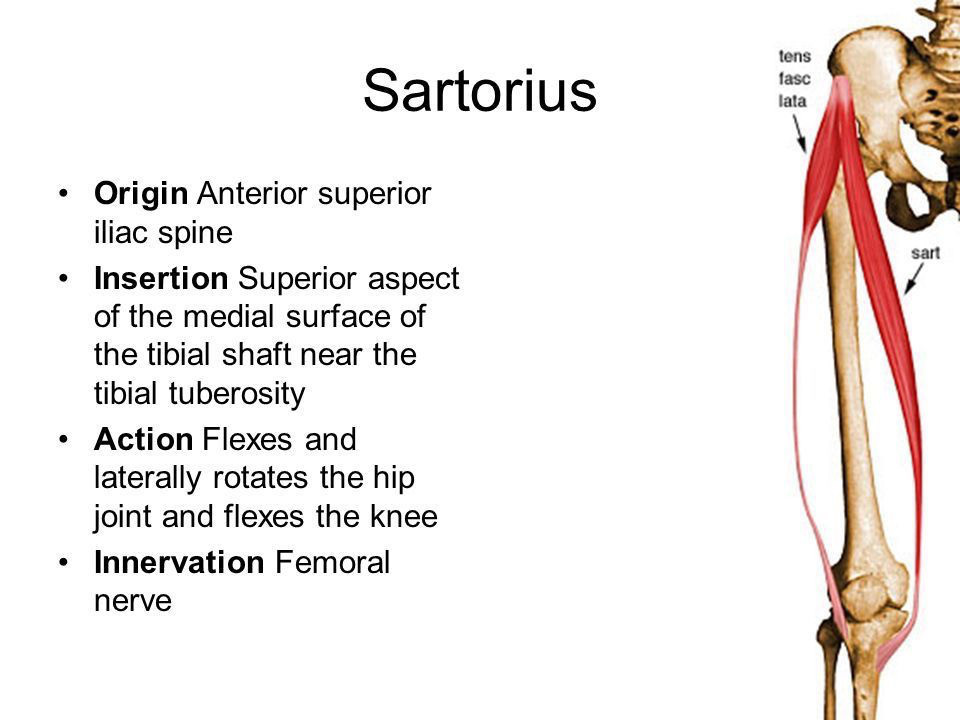

縫工筋 (Sartorius)

縫工筋 (Sartorius)